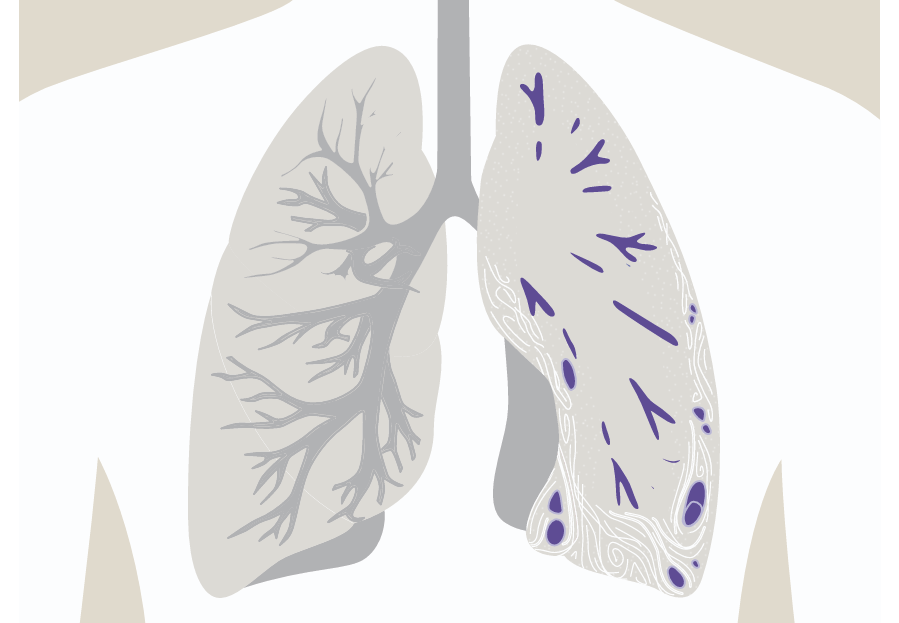

Mitä on keuhkofibroosi?

Tietoa keuhkofibroosista